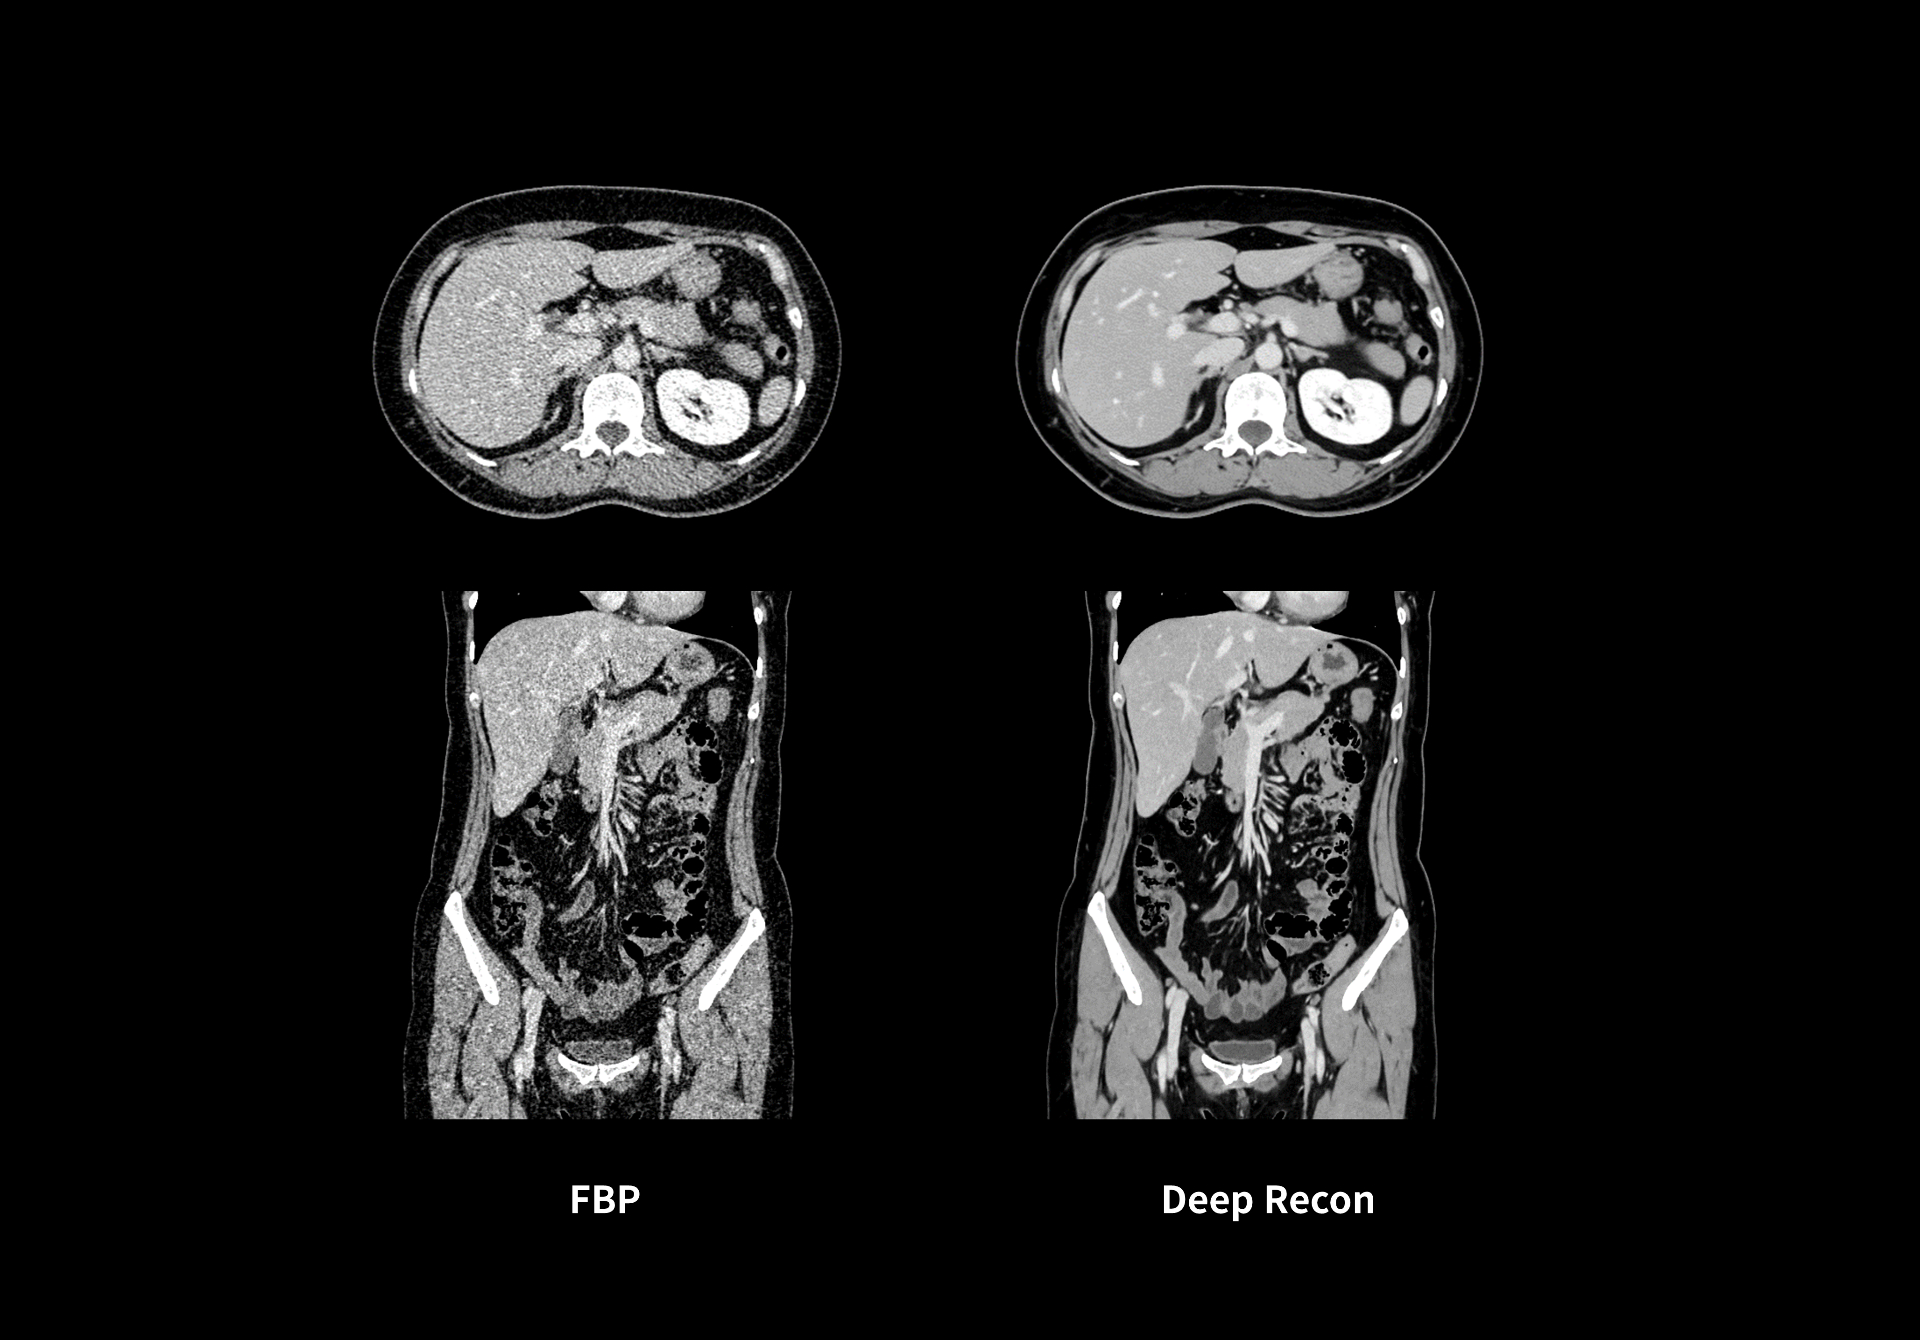

Deep Recon**深度学习重建技术

高降噪

密集连接式网格架构,最大降低98%图像噪声

高保真

全局噪声识别模型,还原真实图像,增强诊断信心

高对比度

同等扫描条件,最大提升151%低密度分辨率

全身临床部位覆盖

百万级训练集,针对不同解剖部位数据建模,覆盖全面临床场景

**仅供科研使用